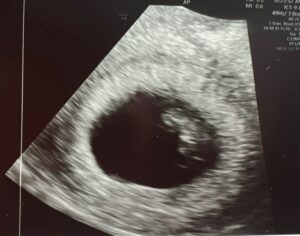

We Have A Baby: 8 Weeks With A Heart Beat!

Baby Is Right Where It Should Be!

I am 8 weeks and the baby’s heart beat is 167 bpm!

Patient age: 36

Tubal ligation type: Tubal clips (clamps)

Patient hometown: Darlington, South Carolina